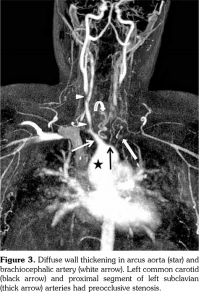

A 14-year-old female patient referred to our clinic with headache and dizziness for two weeks and loss of consciousness for about 10 minutes. On admission, the blood pressure was 90/60 mmHg and all peripheral pulses were palpable. Her body weight was above 97th percentile for her age and body mass index was 33. The fundus examination and other organ systems were essentially normal. Laboratory studies revealed erythrocyte sedimentation rate (ESR) as 108 mm/hour and C-reactive protein (CRP) as 7.5 mg/dL (0-0.8), while other measurements were normal. Urinalysis revealed microscopic hematuria and proteinuria of 31.9 mg/m2/hour in 24-hour urine collection. The cerebrospinal fluid examination showed no abnormalities. Cranial magnetic resonance imaging (MRI) showed multiple millimetric hyperintense deep white matter lesions on T2-weighted imaging (Figure 1). Intracranial and extracranial arteries were normal in magnetic resonance angiography (MRA). Renal biopsy findings were interpreted as FSGS (Figure 2). Patient was considered as cerebral vasculitis and incidental FSGS. Pulse methylprednisolone therapy for three consecutive days was initiated and continued with oral prednisolone. At four years of follow-up, proteinuria decreased to 5-15 mg/m2/hour, and ESR and CRP were normal. Repeated brain MRI and MRA examinations showed no new lesions. Four years later, at the age of 18, on a routine examination, both radial artery pulses were absent and the blood pressure could not be measured. Significant bruit was heard on the left carotid artery. Laboratory studies revealed ESR as 43 mm/hour and CRP as 2.46 mg/dL. Aortic MRA revealed diffuse wall thickening and contrast enhancement in the arcus aorta and its many main branches (Figure 3). Takayasu arteritis diagnosis was established according to the European League Against Rheumatism/ Paediatric Rheumatology International Trials Organisation/Paediatric Rheumatology European Society criteria.[2] Methotrexate was begun, and daily prednisolone was continued. Four months after the diagnosis of TA, left-sided hemiparesis developed. Brain MRI demonstrated a wide cerebral infarct at the right anterior vascular territory (Figure 4). Brain and neck computed tomography angiography showed total occlusion of the right internal carotid artery. Vascular involvement of the right common carotid artery was progressed to preocclusive stenosis. Diameters of the right anterior and middle cerebral arteries were thin and fed by the posterior and anterior communicating arteries (Figure 5). Tocilizumab treatment was started at 8 mg/kg every four weeks. At follow- up with 2.5 years of tocilizumab treatment, the patient's clinical condition improved slightly, and no new symptoms developed. A written informed consent was obtained from the patient.

Renovascular hypertension is the most common renal manifestation of TA; however, proteinuria and nephrotic syndrome are both very rare and usually caused by factors other than FSGS. Four years before the diagnosis of TA, our patient was diagnosed as cerebral vasculitis. In the same period, renal biopsy performed due to proteinuria was reported as FSGS. Cerebral vasculitis and TA in our patient may be coincidental with FSGS but it was supposed that immune complex deposition and vascular lesions caused glomerular ischemia in TA.[7] Kuroda et al.[8] reported a 50-year-old female patient with TA who developed proteinuria and renal dysfunction with glomerulopathy mimicking membranoproliferative glomerulonephritis. They argue that increased vascular endothelial growth factor and interleukin (IL)-6 levels may cause renal disease.

Microvascular involvement might lead to glomerular ischemia and obesity might be an additional factor for developing FSGS in our patient. FSGS is a pattern of histologic injury rather than a disease. In obese patients, elevated plasma levels of leptin through upregulation of transforming growth factor beta 1 may also predispose to glomerulosclerosis.[9]